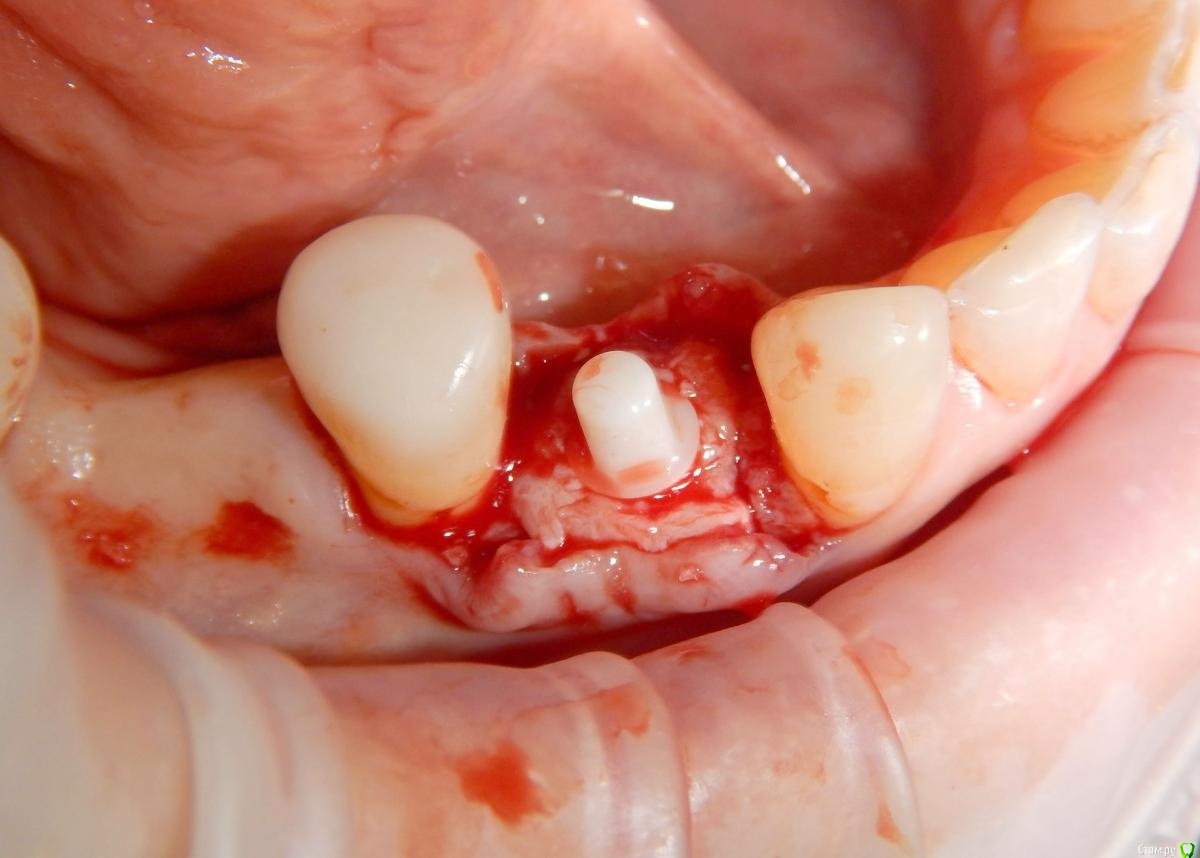

Astronaft Опубликовано 24 января, 2021 Поделиться Опубликовано 24 января, 2021 (изменено) Одиночный цирнокиевый имплантат и расщепление без графта. Пациентка:тонкая хрупкая женщина 55 лет, сконцентрированная на своем здоровье, в некоторой мере мнительная.всегда тяжелые заживления после удалений (по опросам)есть результаты Клиффорд теста (такая книжка под 200 страниц с in vitro аллерго-пробами на все известные материалы) Поставленная цель:только цирконий Мне было интересно найти вариант найболее приемленый пациентке и мне. С минимом хирургического риска и риском сожаления пациентки про выбор костного материала. Во-первых, я не использую аллографты - философски, чужие протеины, неприятный запах - просто основываясь на своем мнении.Во-вторых, мнительные пациенты склонны "пойти и почитать" до или потом и как следствие внушить себе вещи которых может и не было. Но по скольку мысль материальна... Все обсудил заранее.План: ридж сплит (расщепление), имплантат без графта, свободный СТ графт; если случается вестибулярная рецессия - пилим зирконий во рту. Ридж сплит сделан пьезотомом - крестальный и вертикальные пропилы на глубины около 8-10мм.Пилотное сверло.Развдвинул кость остеотомами от 1.6мм до 3.5мм в диаметре.Очень мягкая кость - напомнила мегкую максиллу плотности ногтевой пластинки вестибулярно.Имплант встал легко, но торк 40нсм. СТ графт из области 18. Деэпителизирую скальпелем уже потом. Тут интересно отметить, что я перестал боятся ошметков эпителия.Пончо сверху имплантата (а-ля шашлык Карлоса).Швы. PTFE всегда хорош. 12 недель.Красивая десна.Периотест -5.8 - отличный результат.Оттиск. Циркониевая коронка симметричная другой стороне. Изменено 24 января, 2021 пользователем Astronaft 19 Ссылка на комментарий

Astronaft Опубликовано 25 января, 2021 Автор Поделиться Опубликовано 25 января, 2021 Спасибо.День операции, 12 недель, день цементировки. 3 1 Ссылка на комментарий